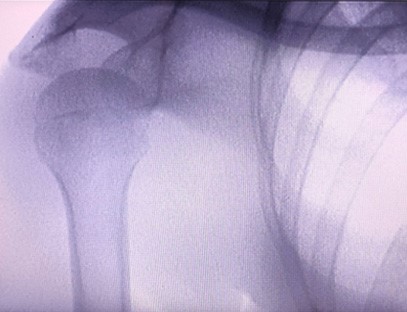

Das tragbare Röntgengerät As-c200 ist ein tragbares Instrument mit geringer Strahlendosis und sehr sicher. Es eignet sich besonders für Einheiten und Einzelpersonen mit unzureichendem Budget und geringen Anforderungen an Bilder. Die neue Generation ist mit einem 10-Zoll-HD-Großbildschirm ausgestattet, der einen größeren Perspektivbereich bietet und die gesamte Handfläche vollständig perspektivisch betrachten kann. Es ist vor allem aus medizinisch-orthopädischer Sicht geeignet. Es kann an einen Foliendrucker angeschlossen werden, um orthopädische Folien zu bedrucken, und kann auch in der industriellen Produktion und Prüfung eingesetzt werden. Keine Dunkelkammer, direkte Perspektive, sofortige Beobachtung, hohe Auflösung und klare Bildgebung.

Bei unserem orthopädischen Röntgengerät handelt es sich um ein hochwertiges Produkt, das speziell für die orthopädische Bildgebung entwickelt wurde. Es kann zur Diagnose und Behandlungsplanung verschiedener orthopädischer Erkrankungen verwendet werden, darunter Frakturen, Luxationen, Arthritis und Knochentumoren. Es ist mit fortschrittlicher Röntgentechnologie ausgestattet, die qualitativ hochwertige Bilder bei reduzierter Strahlenbelastung ermöglicht. Das Gerät verfügt über ein hochauflösendes Bildgebungssystem und kann Bilder jeder Knochenstruktur mit großer Klarheit aufnehmen.

Unser orthopädisches Röntgengerät kann in verschiedenen medizinischen Fachgebieten eingesetzt werden, darunter Orthopädie, Neurologie und Notfallmedizin. Es wird häufig zur fluoroskopischen Beobachtung menschlicher Gliedmaßenknochen, in Veterinär- und Tierkliniken sowie zur Behandlung von Verwundeten an Sportstätten, in Gebäuden, auf Hochseeschiffen, in abgelegenen Gebieten und auf Militärgeländen eingesetzt. Zu den klinischen Anwendungen gehören: